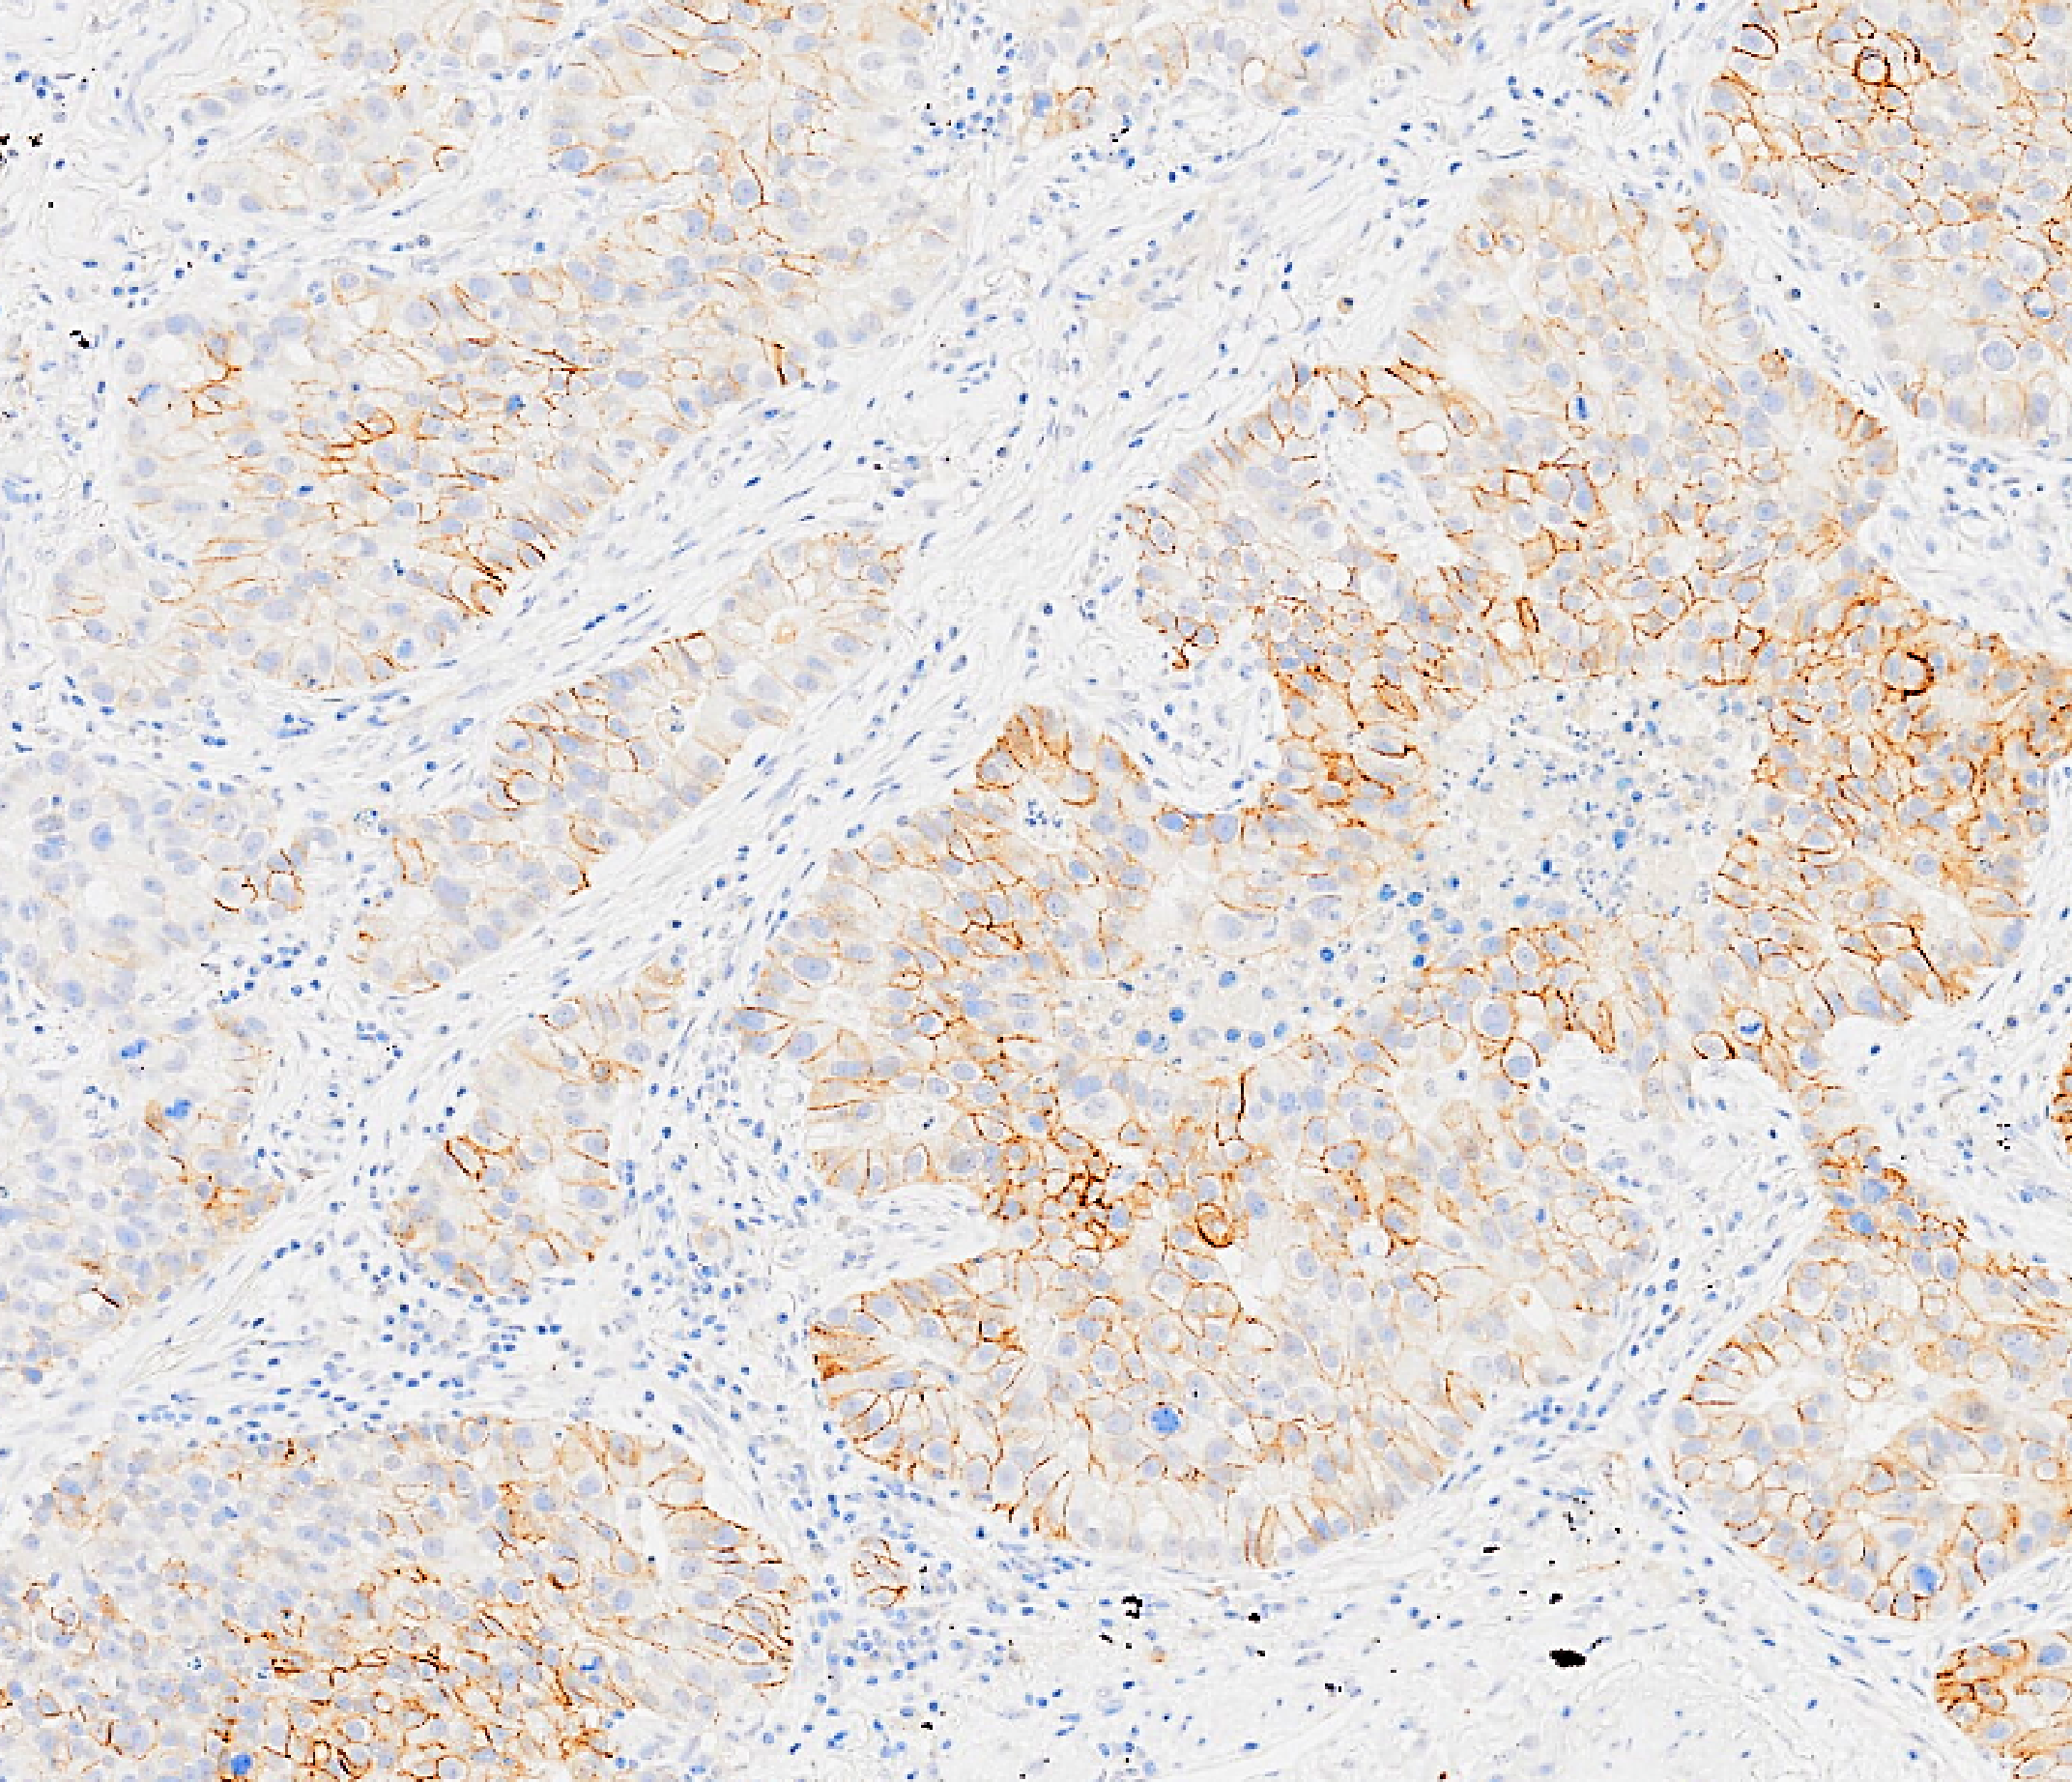

Our research spans the whole spectrum of cancer research from cell biology through to translational and clinical studies

Our research groups study many fundamental questions of cancer biology and treatment

The Institute has outstanding core facilities that offer cutting edge instruments and tailored services from expert staff